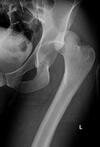

Intracapsular NOF